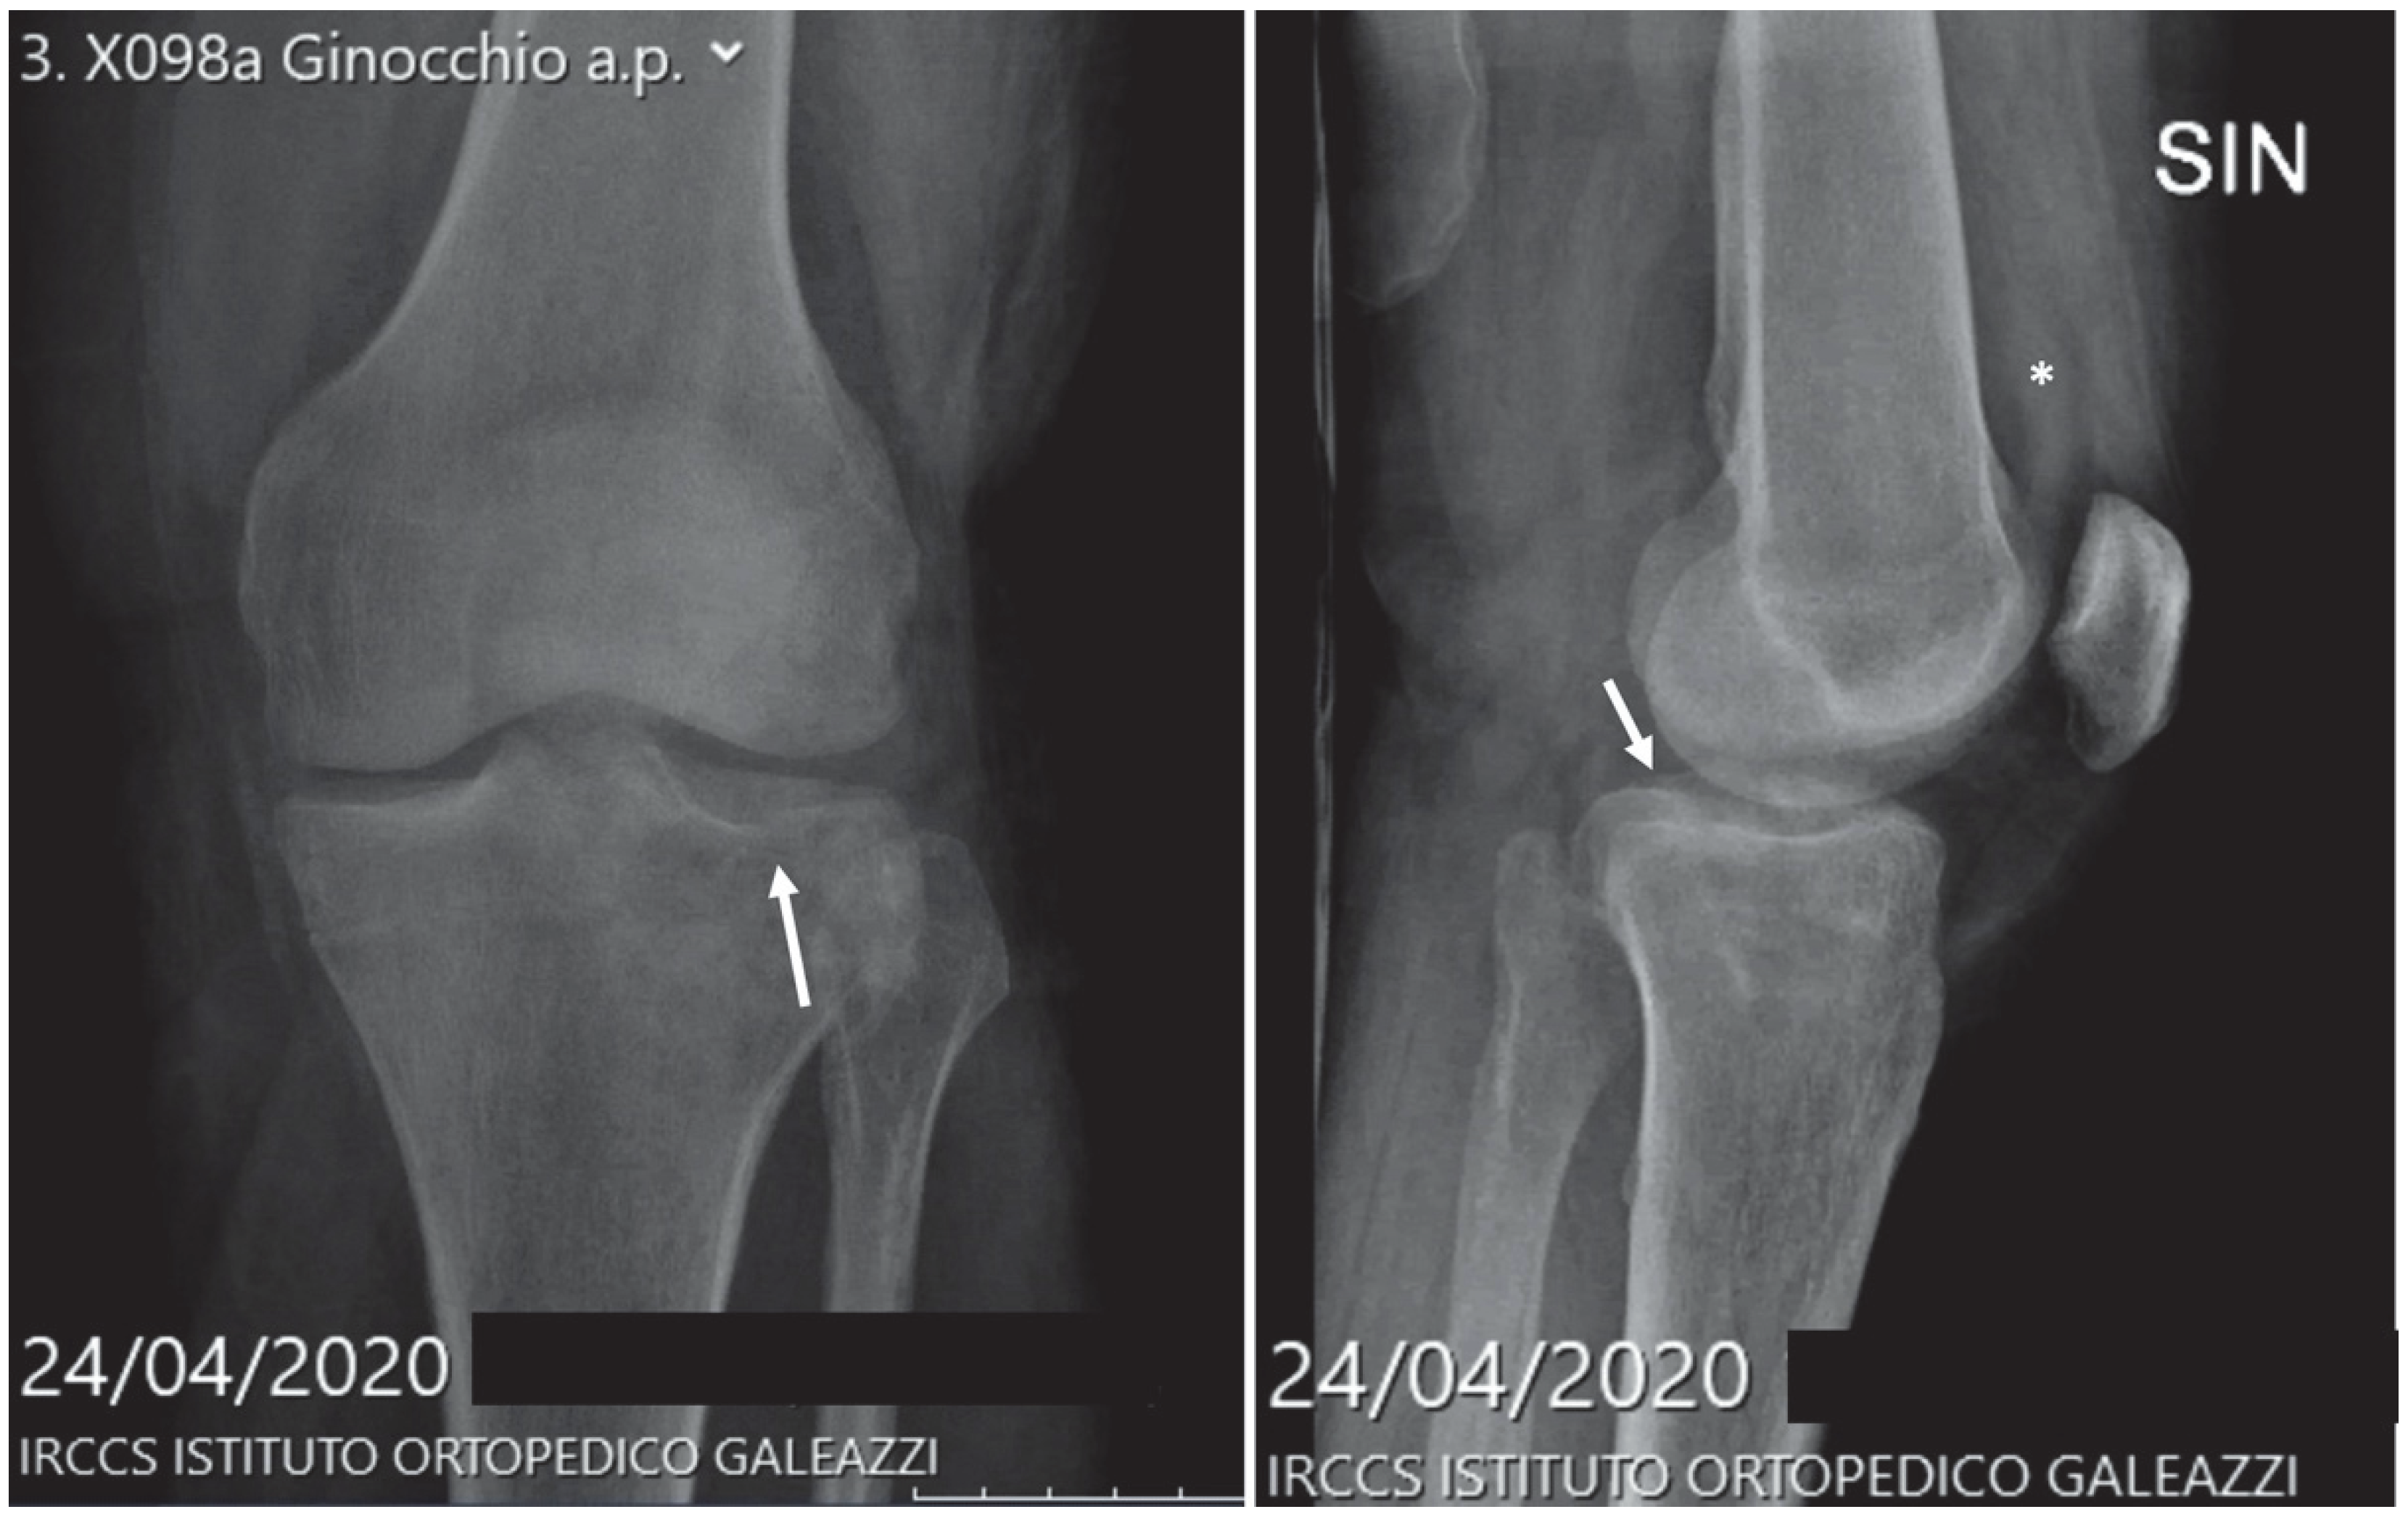

| Bone contusion | 253 | 10.1% | 655 | 14.3% | 898 | 14.3% | 1087 | 13.7% |

| Joint sprain | 343 | 13.6% | 712 | 15.5% | 1561 | 24.9% | 2123 | 26.9% |